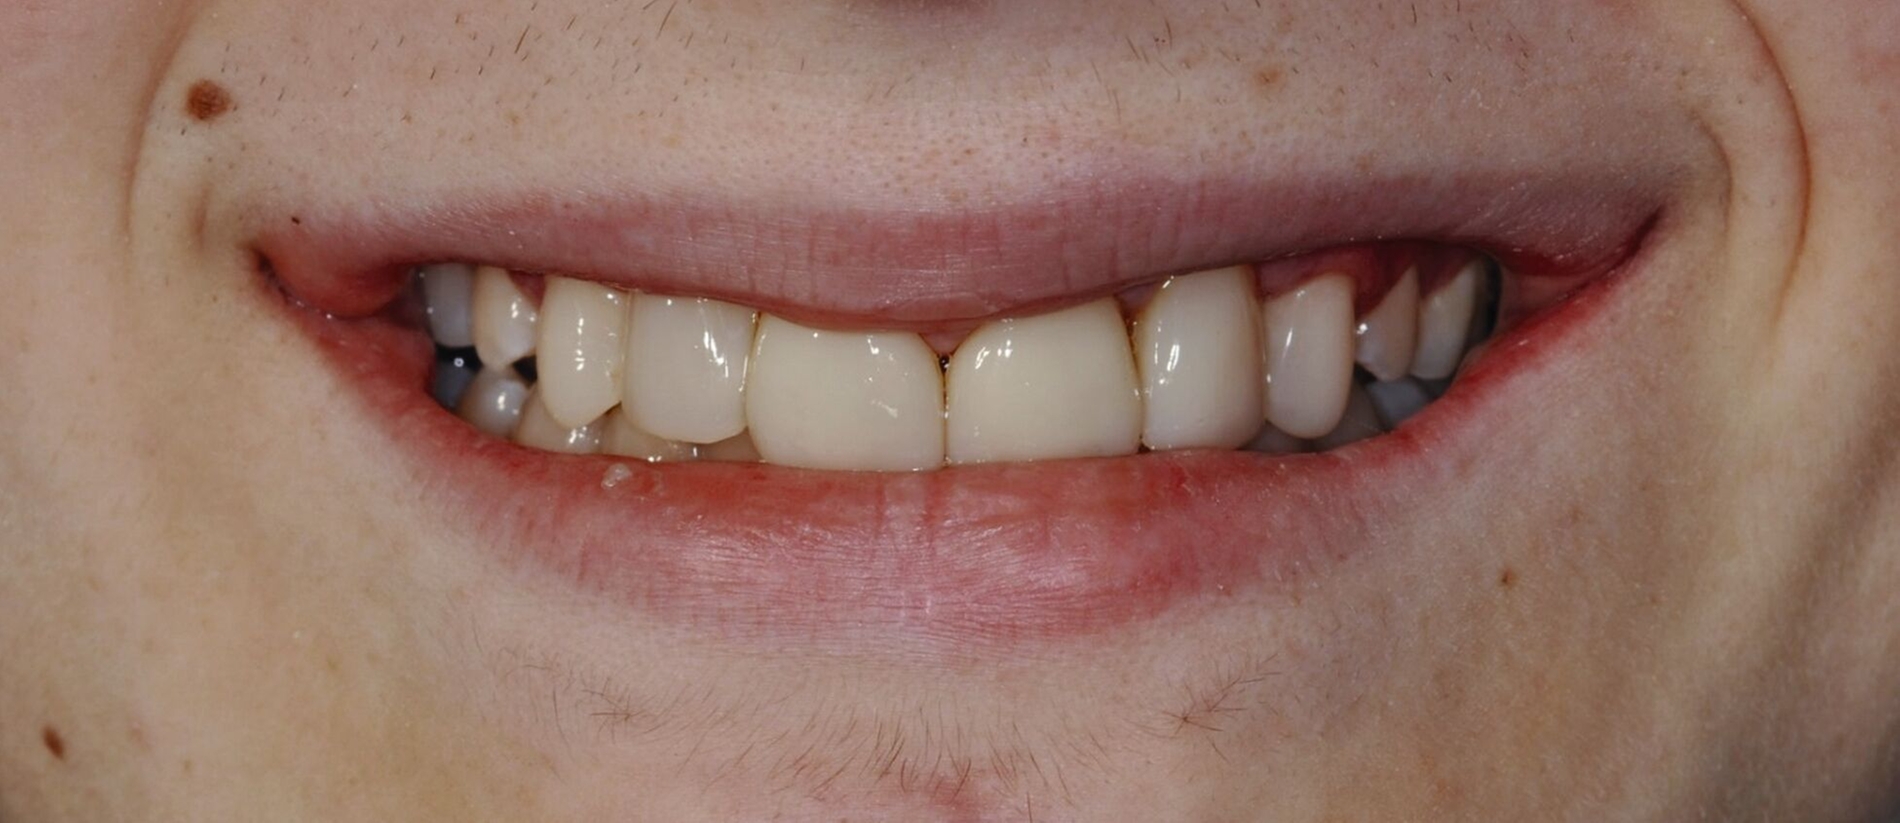

Bei der Erstvorstellung zeigt der Patient ein ausgeprägtes Diastema mediale sowie Restlücken und Asymmetrien im Oberkieferfrontzahnbereich nach kieferorthopädischer Therapie alio loco (Abbildung 1). Aufgrund mangelnder Adhärenz konnten nicht alle kieferorthopädischen Behandlungsziele erreicht werden, was insbesondere aus ästhetischer Sicht Herausforderungen für den restaurativen Lückenschluss mit sich bringt. Erschwerende Faktoren sind die Verschiebung der Mittellinie, die Achsenneigung der Zähne 13, 12, 22 und 23 sowie die inhomogene Lückenverteilung mit ungleich verteilten Lückengrößen (Abbildung 2). Eine erneute kieferorthopädische Korrektur lehnt der Patient allerdings ab. Subjektiv empfindet er insbesondere das kindliche Erscheinungsbild der lückig stehenden, kurz und klein wirkenden seitlichen Schneidezähne als störend. Ziele der Behandlung sind eine präventionsorientierte, ästhetisch-funktionale Rehabilitation des Oberkieferfrontzahnbereichs und eine Harmonisierung des dentofazialen Erscheinungsbildes.